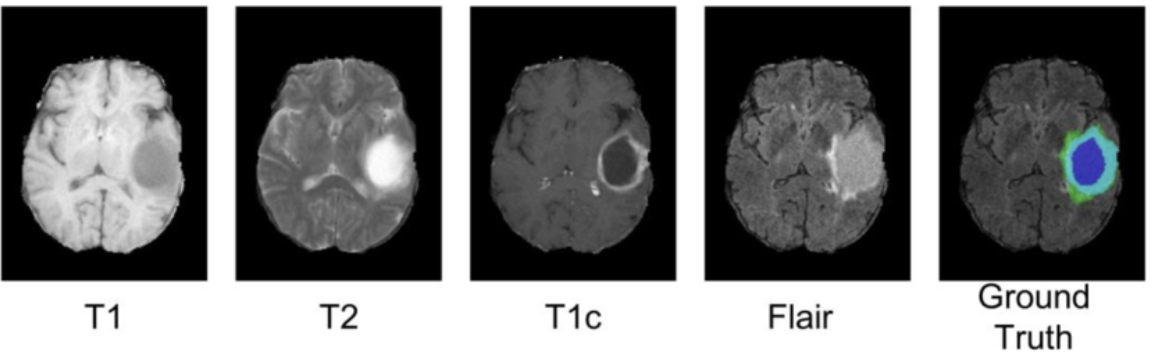

Deep Learning-Based 3D Brain Tumor Segmentation: A Novel Approach for Accurate and Efficient Diagnosis

Brain tumor segmentation is crucial for medical diagnosis and treatment planning, yet manual segmentation remains labor-intensive and inconsistent. This project introduces a Swin-UNETR-based model for automated segmentation, integrating a 3D Swin Transformer, spatial attention mechanism, and squeeze-and-excitation (SE) modules to enhance feature representation and capture long-range dependencies. Evaluated on the BraTS dataset, the model achieved a Dice score of 0.88, outperforming U-Net in detecting complex tumor structures with greater precision.